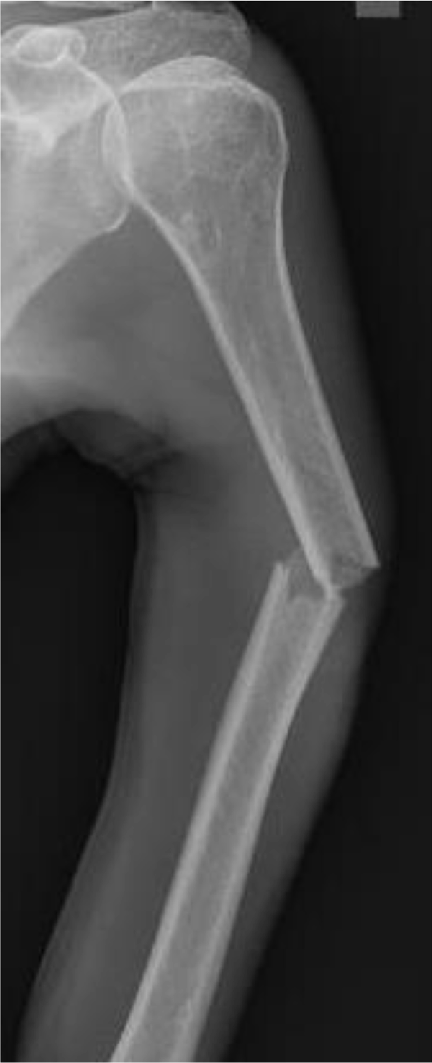

Detects brain tumors, liver disease, heart conditions, and bone fractures using X-rays and MRI scans.

Pre-trained ML and deep learning models for disease detection using medical imaging (CNNs for X-rays and MRIs, classifiers for structured data).